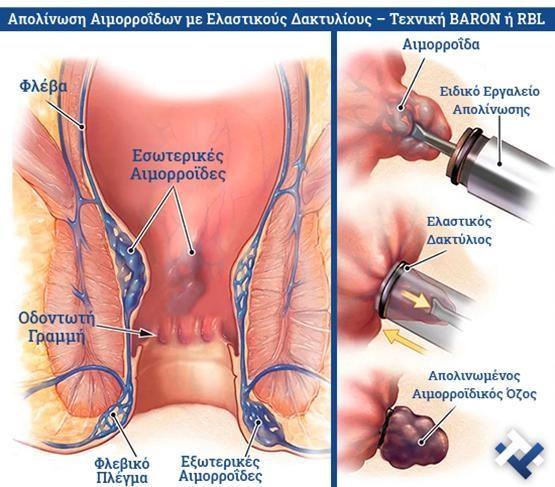

Χειρουργική laser σύγχρονων κυκλικών ινώνΘεραπεία αιμορροϊδων με laser (LHP) Αφαίρεση αιμορροΐδων με υπερήχους (HALL-RAR) Xωρίς χειρουργείο με ελαστικούς δακτυλίους (Τεχνική BARON-RBL)

Xωρίς χειρουργείο με ελαστικούς δακτυλίους (Τεχνική BARON-RBL)

Ο Γενικός Χειρουργός Λιάγκος Γεώργιος MD PhD εκτελεί τις επεμβάσεις Λαπαροσκοπικά, Ενδοσκοπικά, Ανοιχτά Ελάχιστα Επεμβατικά και με Laser. Η θεραπεία εξατομικεύεται σε κάθε ασθενή ανάλογα με τις ανάγκες του. Αναλαμβάνει περιπτώσεις όπως κήλες και κοιλιοκήλες (αντιμετώπιση βουβωνοκήλης, αντιμετώπιση ομφαλοκήλης, θεραπεία επιγαστρικής κήλης, κήλη των αθλητών (Σύνδρομο κοιλιακών προσαγωγών), αντιμετώπιση μετεγχειρητικής κήλης, θεραπεία Μηροκήλης), πέτρες στη χοληδόχο κύστη, λαπαροσκοπική χολοκυστεκτομή, αντιμετώπιση Κύστη Κόκκυγος με λέιζερ (laser), παθήσεις πρωκτού, χειρουργική laser σύγχρονων κυκλικών ινών (αιμορροΐδες αντιμετώπιση, θεραπεία αιμορροϊδων με laser (LHP), αφαίρεση αιμορροΐδων με υπερήχους (HALL-RAR), χωρίς Χειρουργείο με ελαστικούς δακτυλίους (Τεχνική BARON-RBL), θεραπεία ραγάδας πρωκτού (Ραγάδα δακτυλίου), θεραπεία περιεδρικού συριγγίου, θεραπεία περιεδρικού αποστήματος, κονδυλώματα πρωκτού Θεραπεία, δερματικό ράκος (Skin tag) εκτομή, αντιμετώπιση Kνησμού, καρκίνος πρωκτού θεραπεία), παθήσεις Δέρματος, χειρουργική με laser CO2, αφαίρεση μορφωμάτων δέρματος - βιοψίες, αφαίρεση ελιάς (Σπίλου), σμηγματογόνος κύστης θεραπεία, αφαίρεση λιπώματος, είσφρυση όνυχος χειρουργείο, καρκίνος δέρματος θεραπεία, οξεία σκωληκοειδίτιδα, παθήσεις Λεπτού και Παχέος Εντέρου, ειλεός λεπτού εντέρου, εκκολπωμάτωση (Εκκολπωματίτιδα) σιγμοειδούς, καρκίνος παχέος εντέου, κολοστομίες, port χημειοθεραπείας κ.α. εξυπηρετώντας Παγκράτι και γύρω περιοχές.